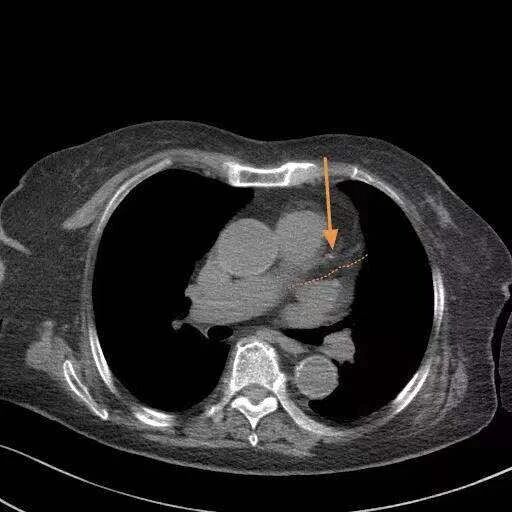

11月26日,山东烟台市莱阳中心医院影像科医生王俊豪在个人平台分享了一个病例:一位91岁的老太太,因为有点头晕、胸疼前来就诊,胸部CT检查时发现她的心脏很年轻。

随着年龄增长,很多人会发生冠状动脉硬化,形成一些软硬斑块,引发冠心病。但这位老人只有很小的一点钙化(如图),比很多60岁的人都要好。而且检查发现,老人肺里没有结节,很干净。①

“影像科豪大夫“图